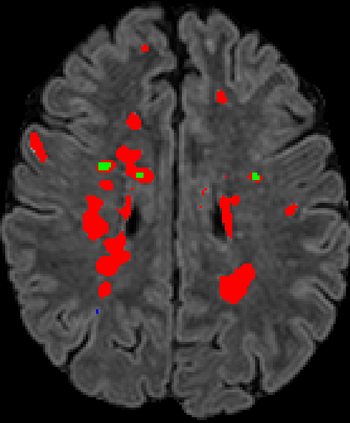

Recently, segmentation methods based on Convolutional Neural Networks (CNNs) showed promising performance in automatic Multiple Sclerosis (MS) lesions segmentation. These techniques have even outperformed human experts in controlled evaluation conditions such as Longitudinal MS Lesion Segmentation Challenge (ISBI Challenge). However state-of-the-art approaches trained to perform well on highly-controlled datasets fail to generalize on clinical data from unseen datasets. Instead of proposing another improvement of the segmentation accuracy, we propose a novel method robust to domain shift and performing well on unseen datasets, called DeepLesionBrain (DLB). This generalization property results from three main contributions. First, DLB is based on a large group of compact 3D CNNs. This spatially distributed strategy ensures a robust prediction despite the risk of generalization failure of some individual networks. Second, DLB includes a new image quality data augmentation to reduce dependency to training data specificity (e.g., acquisition protocol). Finally, to learn a more generalizable representation of MS lesions, we propose a hierarchical specialization learning (HSL). HSL is performed by pre-training a generic network over the whole brain, before using its weights as initialization to locally specialized networks. By this end, DLB learns both generic features extracted at global image level and specific features extracted at local image level. DLB generalization was validated in cross-dataset experiments on MSSEG'16, ISBI challenge, and in-house datasets. During experiments, DLB showed higher segmentation accuracy, better segmentation consistency and greater generalization performance compared to state-of-the-art methods. Therefore, DLB offers a robust framework well-suited for clinical practice.